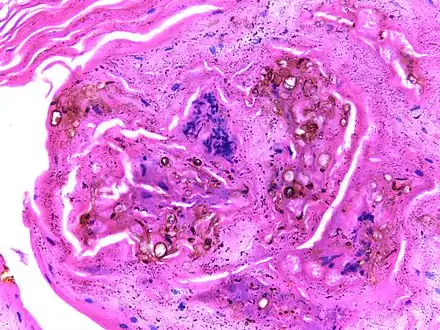

On histology, chromoblastomycosis manifests as pigmented yeasts resembling "copper pennies".[10]

Micrograph of chromoblastomycosis showing sclerotic bodies -